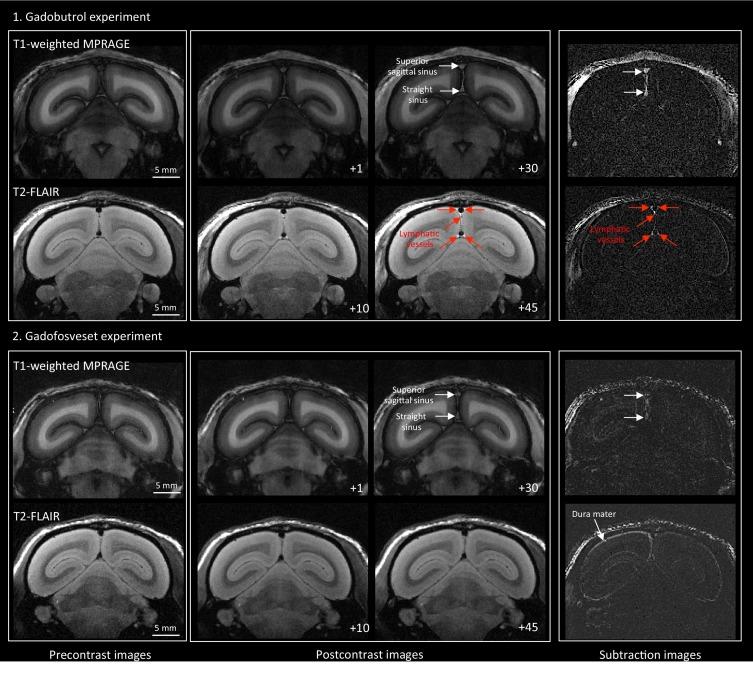

Here, we report the existence of meningeal lymphatic vessels in human and nonhuman primates (common marmoset monkeys) and the feasibility of noninvasively imaging and mapping them in vivo with high-resolution, clinical MRI. On T2-FLAIR and T1-weighted black-blood imaging, lymphatic vessels enhance with gadobutrol, a gadolinium-based contrast agent with high propensity to extravasate across a permeable capillary endothelial barrier, but not with gadofosveset, a blood-pool contrast agent. The topography of these vessels, running alongside dural venous sinuses, recapitulates the meningeal lymphatic system of rodents. In primates, meningeal lymphatics display a typical panel of lymphatic endothelial markers by immunohistochemistry. This discovery holds promise for better understanding the normal physiology of lymphatic drainage from the central nervous system and potential aberrations in neurological diseases.

在这里,我们报告了脑膜淋巴管在人类和非人类灵长类动物(普通狨猴)中的存在,以及使用高分辨率临床 MRI 对其进行非侵入性成像和体内绘图的可行性。在 T2-FLAIR 和 T1 加权黑血成像中,淋巴管增强与钆布醇增强,这是一种具有高倾向穿过可渗透的毛细血管内皮屏障外渗的基于钆的造影剂,但与血池造影剂钆氟塞特不同。这些与硬脑膜静脉窦并行运行的血管的拓扑结构再现了啮齿动物的脑膜淋巴系统。在灵长类动物中,脑膜淋巴管通过免疫组织化学显示出典型的一组淋巴管内皮标志物。这一发现有望更好地理解从中枢神经系统进行淋巴引流的正常生理学以及神经疾病中的潜在异常。